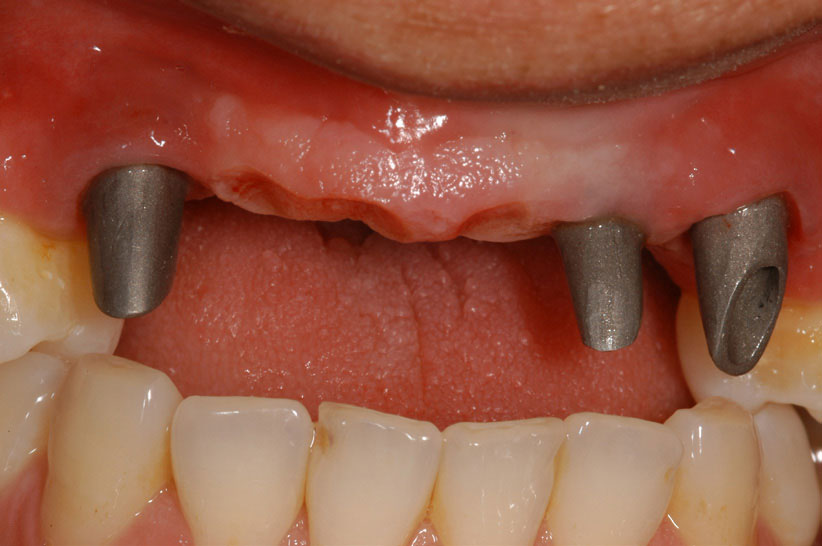

As stated earlier, dentures replace approximately 10% of chewing function. This causes digestive problems due to an inability to chew the food properly, also leading to malnutrition, due to eating only softer, more processed foods. Atrophy of the alveolar arches occurs due to lack of adequate pressure on the bone. This atrophy results in resorption of the tissues leading to mouth sores and tissue irritation. When the denture is allowed to irritate the mental foramen, the patient can experience pain and numbness of the lower lip. A positive solution for a denture patient is to have two to four implants inserted into the alveolar bone. The denture is then connected to the implants via snap-on attachments or a bar resulting in stabilization (Figure 21 through Figure 23). According to the 2002 McGill Consensus Statement on overdentures, mandibular two-implant overdentures are superior to conventional dentures in all clinical trials, even up to 9 years following insertion.36

Because the maxillary arch is wider than the mandibular arch, and the cancellous bone is more porous, four to six implants are utilized for a maxillary overdenture. An advantage of having an implant-supported overdenture in the maxilla is that the palatal area remains uncovered to the soft palate. Having the palate open to the taste buds allows for an enhanced sense of taste. Another advantage is relief from triggering the gag reflex. A properly inserted overdenture can be inserted without adhesives and easily removed, allowing for consistent and thorough cleaning. Finally, it produces better lip support for patients who have experienced bone loss in the anterior area.

Figure 22 – Maxillary bar that attaches the overdenture

Figure 22

Figure 23 – Fully edentulous patient restored with maxillary and mandibular implant supported implants

Figure 23